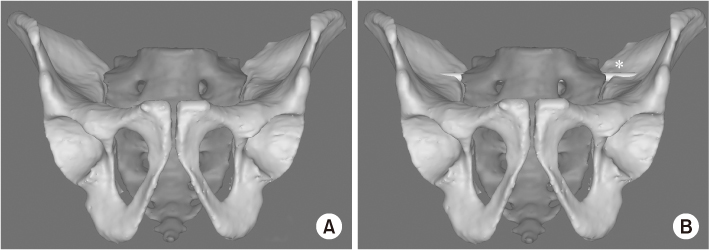

Fig. 1

(A, B) Sacral dysmorphism represents the acute angulation of sacral ala and reduced the corridor for iliosacral screw fixation. *Cortical perforation of screw.